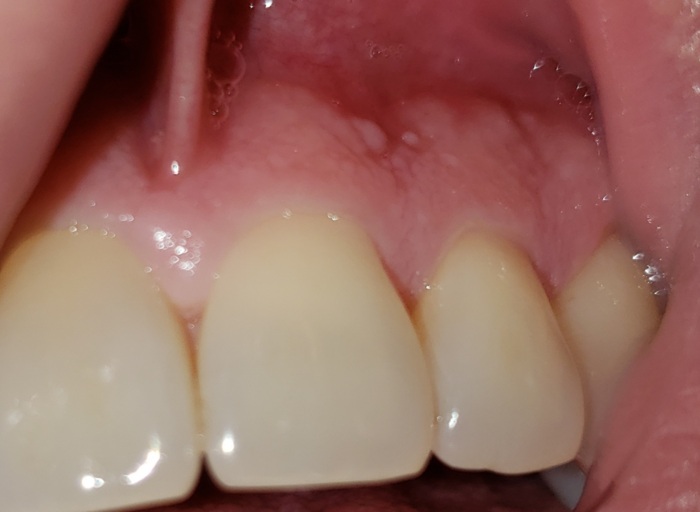

Do these white bumps look to be cause for concern?

I have 2 white round bumps on my upper gum above two of my teeth. It also extends out in a line above a third tooth. They are hard to the touch and aren’t extremely painful on their own unless I really push around on them. They don’t feel like they are going to pop like an abcess, but they recently appeared. Do they look to be cause for concern? The rest of my gums don’t have any kind of bumps like these.

Answer: White Bumps On Tissue

It appears that these round white hard bumps are protrusions of bone, known as buccal exostosis. This extra bone growth is nothing to be concerned about at this time, as long as you are not in any pain. Most dentists consider the bone a variation of normal anatomy, rather than a disease. It is unclear on the causes, however many feel bruxism (grinding and clenching) as well as genetic factors has something to do with it. It is hard to know for sure with a picture alone, so its best to mention this area at your next routine dental visit. Your dentist will be able to identify and give you the exact diagnosis.